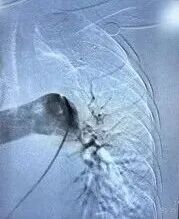

追加注入肝素2000u,于右股静脉交换置入18F鞘管,沿加硬导丝送入腾复血栓抽吸导管于左下肺动脉,行负压抽吸可抽出较多暗红色血栓,送入肺动脉取栓支架系统于左下肺动脉行取栓术,可取出较多暗红色血栓。复查造影提示左下肺动脉未见明显血栓,血流明显改善,测得肺动脉压力下降至40/3mmHg。

取栓中

术后造影